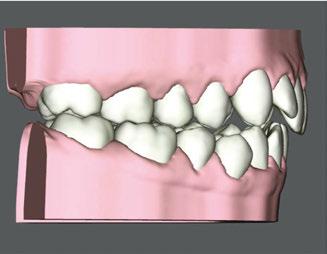

Clear Aligner Therapy (Figures 7, 8, 9)

Our orthodontic goals were the following:

1. Expand upper arch, correct crossbite

2. Close anterior open bite

3. Correct crowding

Patient J was prescribed a series of 43 aligners, with each aligner being worn for 20 hours a day for 1 week.

Figure 7: Digital view of right side before treatment

Figure 8: Digital anterior view before clear aligner treatment

Figure 9: Digital view of left side before treatment. Anterior open bite

Figure 10: Anterior view with elastic buttons to close open bite in conjunction with clear aligners

Figure 11: Right side with elastic buttons for treatment in conjunction with clear aligners